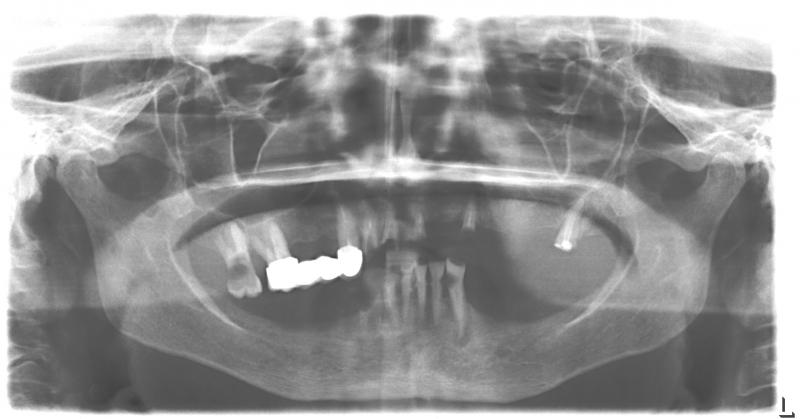

| Фото →Установка 10 имплантантов на беззубую челюсть с помощью компьютерной программы: Через 2 недели после операции |